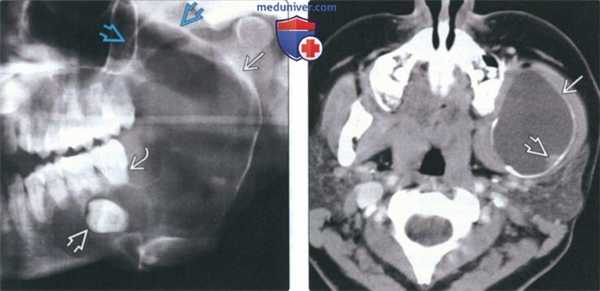

(Слева) На панорамной рентгенограмме в нижней челюсти слева определяется крупная у ни кистозная амелобластома, хорошо отграниченная кортикальной пла стинкой на периферии. Амелобластома выглядит многокамерной из-за фестончатых краев. Обратите внимание на вовлечение венечного отростка. Также определяется смещение треть его моляра с резорбцией корня.

(Справа) На аксиальной КТ с КУ у этого же пациента определяется вздутие кортикальных пластинок. Низкая плотность образования позволяет предположить кисту, однако контрастирующийся муральный узел является ключом к правильному диагнозу.

(Слева) На панорамной реформатированной КЛКТ в нижней челюсти справа определяется уникистозная амелобластома. Обратите внимание на эксцентрическое вовлечение импактного третьего моляра и деструкцию нижнего края ветви.

(Справа) На корональной КТ у мужчины 62 лет определяются характерные признаки амелобластомы десмопластического типа в верхних отделах патологического очага. Множественные мелкие камеры разделены толстыми перегородками и грубыми вкраплениями костной ткани. Этот тип амелобластомы может напоминать фиброзно-костное поражение.